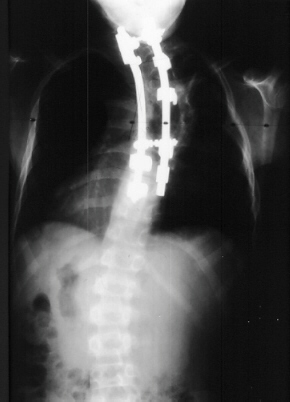

Coinciding with current literature recommendations for treatment of severe dysplastic kyphoscoliosis, the patient underwent an Anterior-Posterior spinal fusion from T1-T10. The scoliosis was corrected to 21 degrees and kyphosis to 34 degrees. The procedure was augmented with a rib strut graft and was tolerated well. No neurologic complications occurred and the patient developed a solid fusion by one year without progression of the curvature. He is currently 5 years post-op playing in sports and without pain.